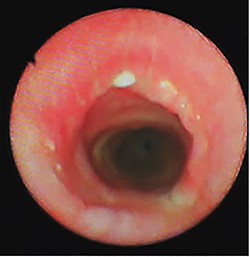

Four weeks later, a control bronchoscopy showed a normal healing process, without stenosis or tumor persistence at the surgical site (Fig. 4). Two months after surgery, the patient resumed her daily life activities. At present, 14 months since the procedure, the patient continues asymptomatic, with a normal functional status, and still under clinical surveillance without local recurrence.

Bronchoscopy view at the tumoral resection site after 4 weeks from surgery.